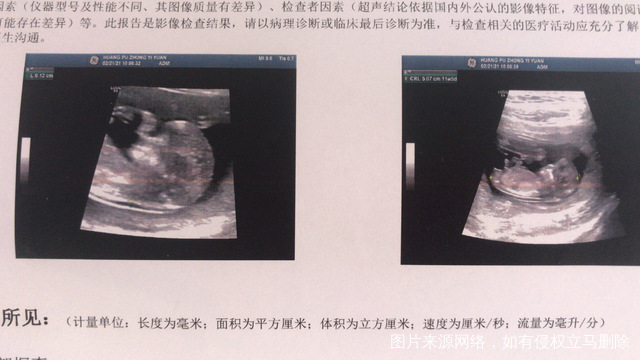

你好医生,做NT的时候,B超显示,胎膜部分剥离,绒毛下出血,请问严重吗?